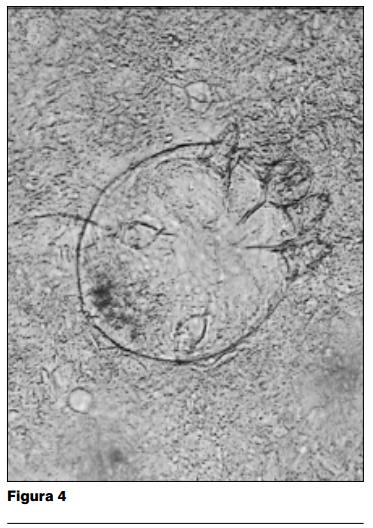

Paraclínica: el examen directo en fresco con KOH al 20%, entre porta y cubreobjeto del material obtenido por escarificacion de las lesiones, muestra abundante cantidad de Sarcoptes scabiei var. hominis en diferentes estadios evolutivos (figuras 3 y 4). El estudio bacteriológico de las lesiones desarrolló Staphylococcus aureus y Streptococcus beta hemolítico.

Las características semiológicas de las lesiones cutáneas nos llevan a la fuerte presunción diagnóstica de una forma clínica particular de escabiosis, la sarna costrosa. Ésta es confirmada al examen parasitológico por dos hechos: en primer término la enorme cantidad de ácaros en la muestra, y en segundo lugar la coexistencia de diferentes estados evolutivos del sarcoptes en un mismo campo microscópico (figura 4). En las formas habituales de presentación de la escabiosis, el estudio parasitológico muestra muy pocos ácaros, y es excepcional que se pueda visualizar en un mismo campo microscópico al mismo tiempo huevos, formas juveniles, adultos y restos parasitarios. Sin duda, esta elevada proliferación de ácaros es responsable de la alta contagiosidad de esta forma particular de sarna, así como de las epidemias intrahospitalarias y en el seno de las colectividades que es capaz de producir (12).